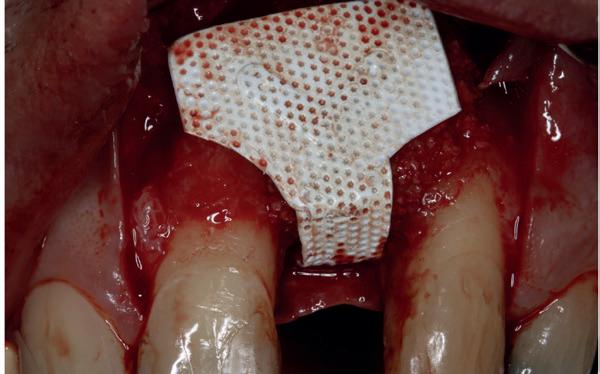

• Aanvulling zachte weefsels met de VISTA techniek en een vrij gingivatransplantaat uit het palatum links en direct dragen van de essix retainer

Voor de aanvulling zachte weefsels chirurgie werd gekozen voor de VISTA techniek, hierbij worden er twee incisies partial thickness flap hoog in de mucosa gemaakt, waarna er ruimte vanuit de incisies wordt getunneld tussen de gingiva en het periost door middel van VISTA tunnel instrumenten. Uit het palatum links werd een vrij gingivatransplantaat geoogst van 15x10 mm met een dikte van 3 mm, die voor inhechten werd geëpithelialiseerd. Als het epitheel niet wordt verwijderd, kan deze graft door

de mucosa heen groeien, dat ten koste gaat van de esthetiek. In het donorgebied wordt een collageen spons ingehecht, waardoor de patiënt daar minder last van heeft. Het bindweefsel wordt door de hul-

pincisies met hechtingen naar het buccale en coronale deel getrokken en aldaar ingehecht. Met twee incisies werd ook de emergence profile gecreëerd (afbeelding 6-13). Voor een goede genezing van het

6. VISTA techniek twee hulp incisies

7. Vervaardiging tunnel met tunnelinstrumenten

8. Geoogst bindweefseltransplantaat uit palatum

9. Na de-epithelialiseren van transplantaat

10. Inhechten van een collageenspons in het donorgebied

11. Middels hechtingen het op de juiste plek trekken van het transplantaat

12. Transplantaat ingehecht

13. Occlusaal beeld verdikking van de zachte weefsels